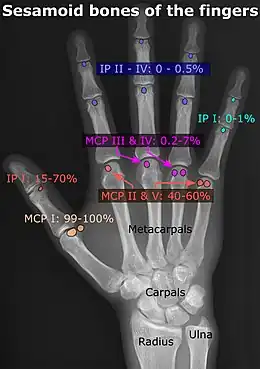

- Location and structure: Erica Chu, Donald Resnick, « MRI Web Clinic — June 2014: Sesamoid Bones: Normal and Abnormal » (consulté le )

- Prevalences: Chen W, Cheng J, Sun R et Zhang Z, « Prevalence and variation of sesamoid bones in the hand: a multi-center radiographic study. », Int J Clin Exp Med, vol. 8, no 7, , p. 11721–6 (PMID 26380010, PMCID 4565393) - ↑ « Poster Abstracts », Association for Sports Medicine of Serbia (Udruženje za medicinu sporta Srbije), (consulté le ), citing: Natsis K., Beletsiotis A., Terzidis I. et Gigis P., « A study of the accessory bones of the foot. Incidence in the Greek population-clinical significance »